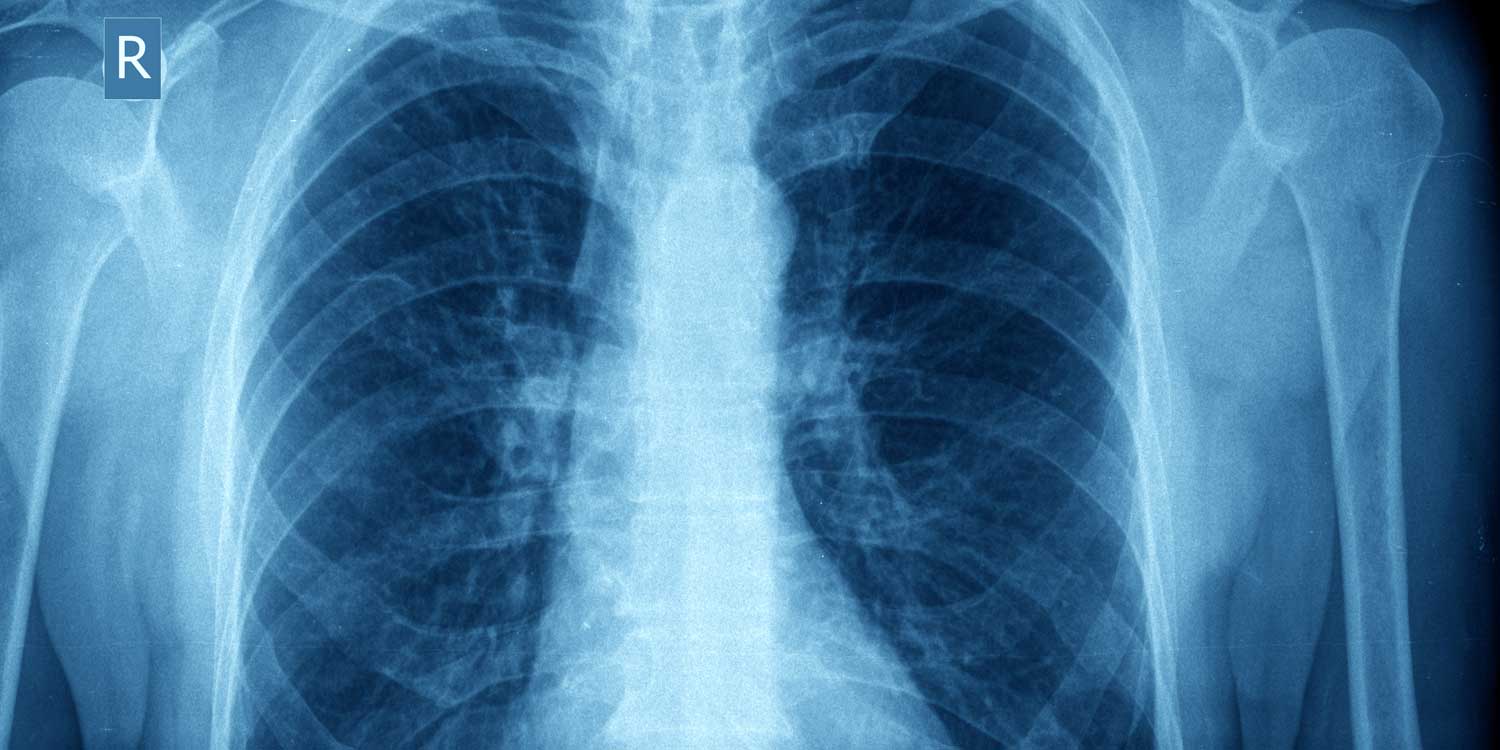

A chest X-ray creates images by passing a controlled beam of low-dose radiation through your chest. Dense structures like bone and the heart absorb most of the radiation and appear white; air-filled lungs absorb very little and appear dark; soft tissues and fluids fall in between, showing as shades of gray. This contrast allows your radiologist to evaluate the following in a single study:

A standard PA (posterior-anterior) chest X-ray shows the lungs as dark fields on either side of the white cardiac silhouette, with the ribs and diaphragm clearly visible. IPMC’s digital system captures this in seconds with minimal radiation.

A normal chest X-ray shows clear lung fields, a heart of normal size, sharply defined ribs and diaphragm, and no visible masses, nodules, or fluid accumulation.